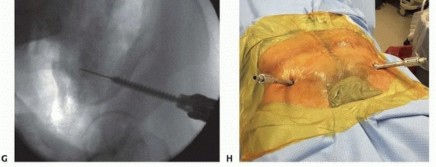

This requires that the drill be held more cephalad (directed caudad) than expected to allow proper position within the desired supra-acetabular bone (superior and cephalad to the acetabulum) rather than the thin bone of the ilium. Triple cannulated drill sleeves are used to protect soft tissues. The fixation pin is inserted, allowing the cortical walls of the ilium to establish direction. An image intensifier may aid in elective nonemergent fixator application. 2. ## Supra-acetabular Technique The patient is positioned supine on a radiolucent table. Safe introduction and proper positioning of the pin require the assistance of fluoroscopic guidance. The open approach for pin placement begins with a vertically oriented 5- to 10-cm incision, depending on patient body habitus and prereduction pelvic deformity. A smaller transverse incision has been described in addition to entirely percutaneous techniques of pin insertion. This vertical approach begins along the lateral border of the anterior superior iliac spine, extending distally and lateral to the AIIS. The interval between the sartorius and tensor fascia lata is identified ( TECH FIG 4A). Tissue planes are developed with blunt dissection and the anterior inferior spine is palpated. The lateral femoral cutaneous nerve is most commonly identified medial to the anterior iliac spine. Anatomic studies have demonstrated the lateral femoral cutaneous nerve to have a variable course, often within 10 mm of inserted pins. 6 With blunt dissection and the use of protective drill sleeves, the lateral femoral cutaneous nerve may be adequately protected. Supra-acetabular pins should be inserted no less than 2 cm proximal to the joint to avoid intra-articular penetration. Capsular extension of the hip may be up to 16 mm superiorly.

An obturator oblique view with slight cephalad angulation

(obturator outlet view) is first obtained. A metallic marker is positioned 2 cm proximal to the hip joint under fluoroscopic control ( TECH FIG 4B). The trocar assembly is positioned under fluoroscopic control superior to the hip joint. Only the outer cortex is drilled. A triple cannulated guide facilitates atraumatic drill and pin insertion. The drill, followed by the pin, is directed within the pelvis, avoiding intra-articular penetration of the hip joint.

Pin angulation is typically 20 degrees medial from the vertical axis and slightly cephalad. The drill is directed toward and superior to the sciatic notch (30 to 45 degrees in the sagittal plane). Fluoroscopic guidance (iliac oblique view with slight cephalad angulation) ensures proper pin trajectory and depth of insertion ( TECH FIG 4C,D).